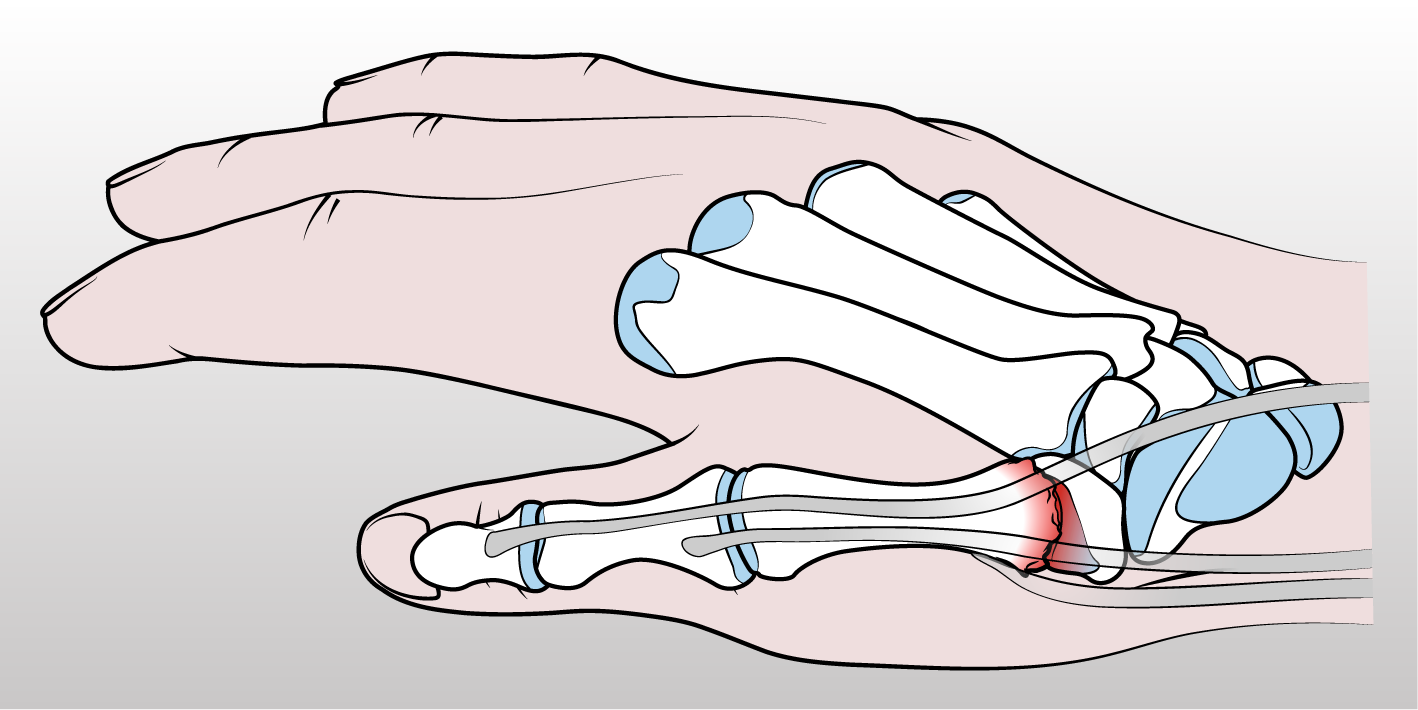

(2) Trapeziectomia con Artroplastica di sospensione: Rimozione del trapezio e ricostruzione dell'articolazione usando una parte dell’abduttore lungo del pollice. Questo intervento mantiene una buona funzione articolare ma riduce la forza. Dopo l'intervento, è necessario indossare un’immobilizzazione per 30 giorni e successivamente eseguire ciclo di fisioterapia. La completa ripresa dell’attività con miglioramento funzionale si avrà circa a 12 settimane dall’intervento.

Figura 3 - Raffigurazione di trapezioctomia con artroplastica di sospensione